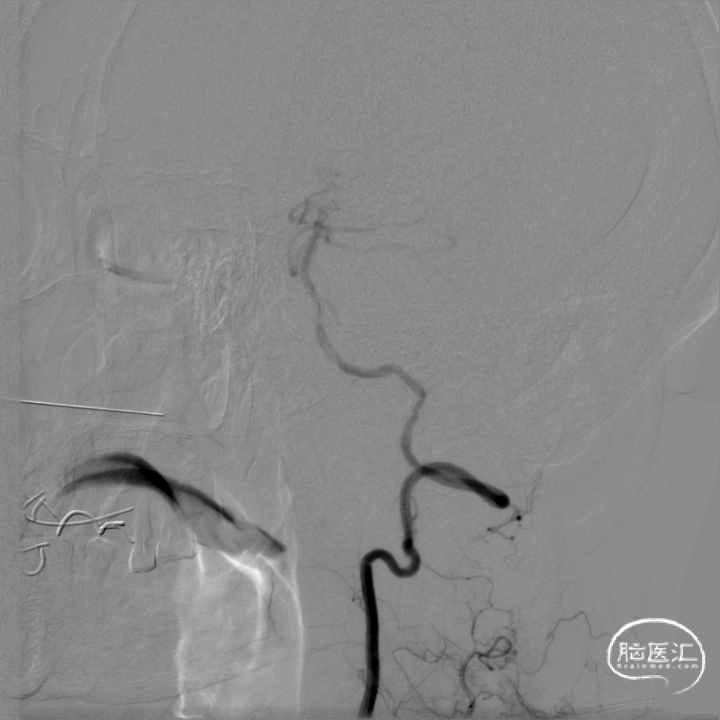

将微导丝头端置右侧大脑后动脉,沿微导丝引入2.0*10mm球囊,小心扩张狭窄段,撤出球囊后造影,原有狭窄较前稍好转,沿微导丝引入支架用微导管置于基底动脉,撤出微导丝,保留微导管,沿微导管引入3.5*15mm Neuroform EZ支架,缓慢释放,复查造影,狭窄较前明显好转,支架贴壁良好。

复查Dyna CT,颅内未见出血及造影剂外渗。